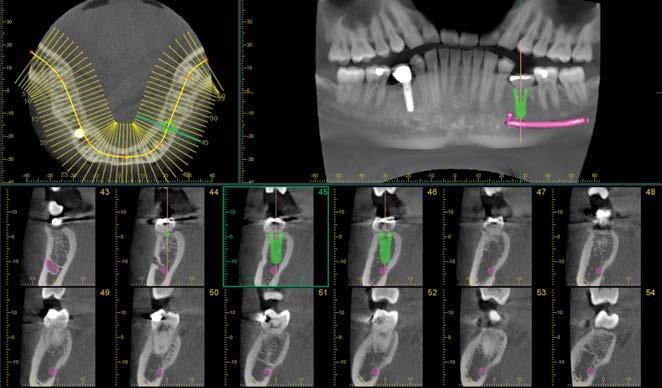

Planungsprozess

Das erfolgreiche Einsetzen von Implantaten beginnt mit dem sehr kritischen und detaillierten Planungsprozess. Hierzu müssen Strukturen, wie Sinusbogen und Mandibularkanal, identifiziert werden. Außerdem ist eine scharfe Aufnahme vom Knochen erforderlich.

Dank der Abbildung des kompletten Kieferbogens, bestechend scharfen Aufnahmen und geringer Strahlendosis für den Patienten ist Veraviewepocs 3D R100 ideal geeignet für die Planung von Implantaten.

Software

Die Software i-Dixel bietet moderne Planungsmöglichkeiten für Implantate sowie die Kompatibilität mit gängiger Drittsoftware.

cMPR-Darstellung

Erstellung von Querschnitten des Kieferbogens.

Ermittlung des Mandibularkanals

Der Mandibularkanal kann zur besseren Ansicht markiert werden, um den Abstand zum Implantat zu messen und die bukkale sowie linguale Position zu bestimmen.